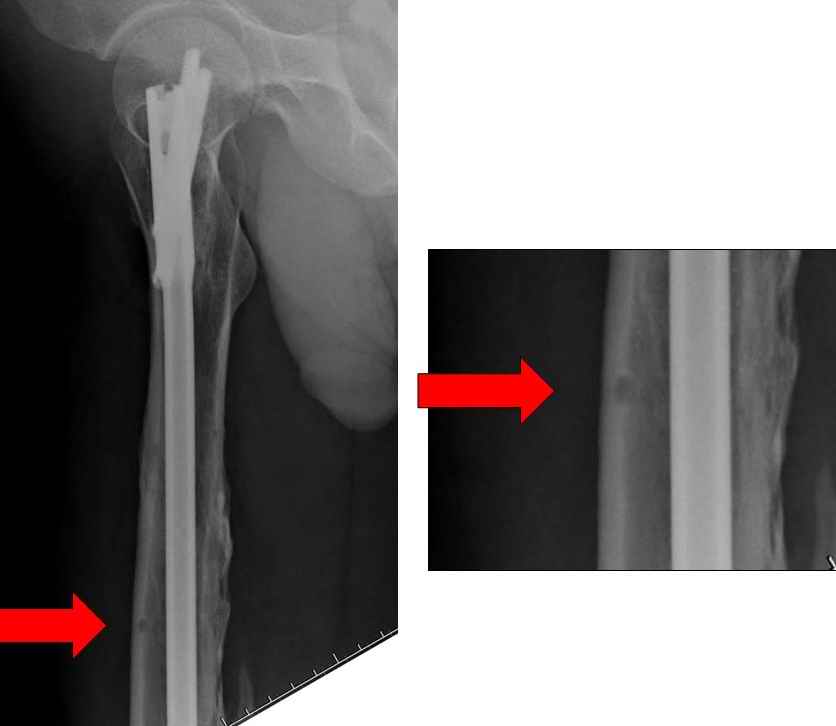

Представляю снимки больного с политравмой: леченного в другом мед.учреждении по поводу открытого перелома бедра, сперва аппаратом наружной фиксации, затем пластиной. Обратился к нам через 8 месяцев после удаления пластины с проблемой несросщего перелома бедренной кости, без клинических проявлении к инфицированию (не все снимки сохранены)

Рутинный интрамедуллярный остеосинтез с расверливанием и с фиксацией реконструктивным трокантерик штифтом (рис №1, №2),

если первые 4 месяца послеоперационного периода проходил без проблем, но на 5 месяце появились боли в дистальном отделе бедра и температура, т.е. симптомы медуллярного инфицирования (рис №3, №4).

Замена реконструктивного штифта “Custom made Nail” с антибиотиком (рис №5, №6),

после промывки канала с рассверливанием внутреннего кортекса, через 4 недели антибиотический штифт удалили, оспалителный процесс остановлен и бедро сросся.

Мы не дождались “Happy End”, у больного IQ в пределах 70%, через 6 месяцев вернулся после небольшой травмы, споткнувшись получил перелом

того же бедра (рис №7).

На следующий день произвели интрамедуллярный остеосинтез: этапы во время операции (рис №8, №9)

и последующих снимках (рис №10, 11, 12, 13) перелом сростается и передвигается с полной нагрузкой.

При обзоре причин перелома, на снимке №2 обнаружили, что один из стержней аппарата наружной фиксации проходил только через передний кортекальный слой, что создало стрессовую зону на бедре и в результате перелом из-за незначительной травмы.

На снимке N2 виден канал от стержня во фронтальной плоскости, на уровне которого на снимке N7 уже перелом.

>дистальный статический винт не доходит до второго кортикала “

Снимок №4 сделан после несостоятельности интрамедуллярного штифта, осложнения инфекцией канала и после миграции шурупов. Я имел ввиду, что снимок № 2 после удаления наружного фиксатора в интрамедуллярном варианте, на увеличенном снимке дырка на переднем кортексе (см. снимок) stress zone Чтобы правильно без осложнений провести half pins, необходимо соблюсти нескольких правил, во первых, они должны вводится в середине диаметра кости с предварительным просверливанием. Во время просверливания кости, сверло проходит первый, потом второй дальний кортекс и стержен вводится вручную. А иногда сверление проходит по касательной к кортексу, нагреваются местные ткани, создается ожог и локальный некроз. Или как будто делается кортикотомия с помощью сверла, как при

методе Илизарова, ослабляя кортикальный слой. Создается стрессовая зона, которая при незначительной травме может осложниться стрессовым

переломом.